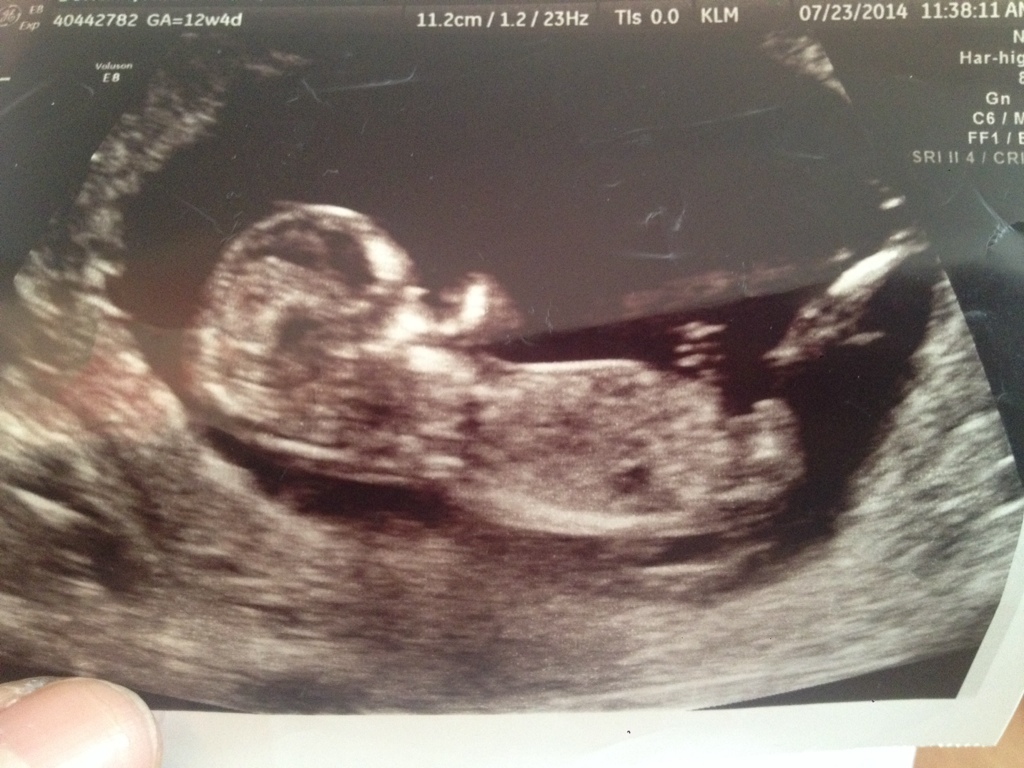

I think boy!

How far along? Looks like a boy.

Maybe girl

Boyish nub

Boy?